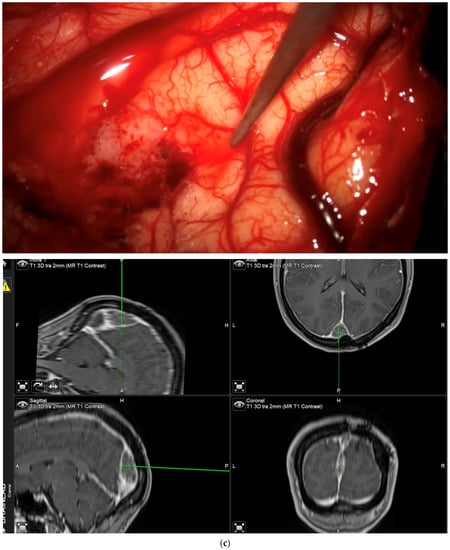

After clearing a field from tumor under white light, with the surgeon no longer being able to identify residual tumor in that field of view, the surgeon has the possibility of switching to blue light to determine whether any pathological tissue can be identified based on fluorescence. If the surgeon finds residual fluorescing tissue after switching to blue light, this area is pointed out using the neuronavigation pointer (and a navigation screenshot is taken). A biopsy is taken from the exact same region after switching back to white light if this can be performed safely. This procedure is also recorded by video from beginning to end. Such interrogations might be performed at multiple stages of surgery, provided a particular area (field of view) has been cleared of tumor according to the impression of the surgeon under white light. The interrogation of an inconspicuous bone flap also constitutes an “end of surgery” scenario if the surgeon wants to rule out any tumor infiltration in the bone. If any fluorescent bone is encountered, then this is biopsied prior to drilling of the bone flap (Figure 3).

“End of surgery” biopsy: After clearing a field from tumor under white light, with the surgeon no longer being able to identify residual tumor in that field of view, the surgeon switches to blue light to determine whether any pathological tissue can be identified based on fluorescence. Any fluorescing tissue is pointed out using the neuronavigation pointer (and a navigation screenshot is taken). A biopsy is then taken collected. This procedure is recorded by video from beginning to end. (a) After dissecting tumor from the brain, the brain is considered free of tumor. (b) Various areas of fluorescence can be observed. The surgeon would then resect the fluorescing tissue shown. (c) Navigation pointer and corresponding screenshot (“F”: footwards; “H”: headward; “A”: anterior; “P”: posterior; “L”: left; “R”: right).